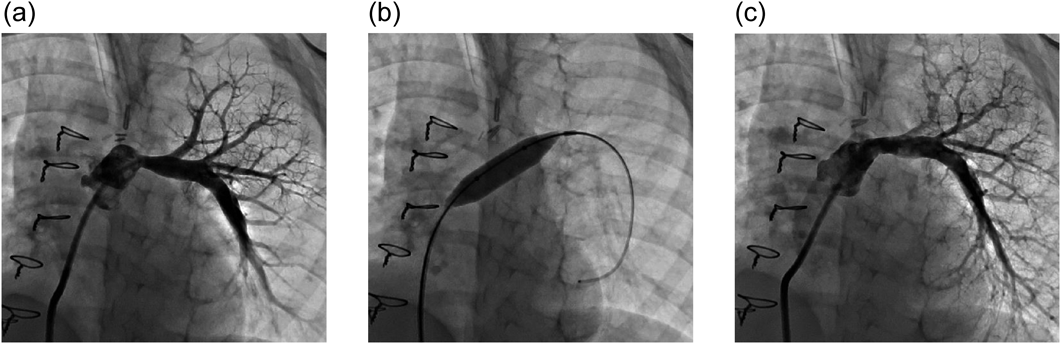

Fig. 1に先天性肺動脈弁狭窄症に対しPTPVを行った8か月男児例を示す.弁尖はドーム状となっており,弁輪径は9.1 mmであった.径12 mmのバルーンをNPで拡張し,狭窄の消失を確認した.PTPV後,右室–肺動脈圧較差は42 mmHgから25 mmHgに改善した.

Fig. 1 An 8-month-old male infant with pulmonary valve stenosis

(a) The pulmonary valve appears dome-shaped. (b) Percutaneous pulmonary valvuloplasty using standard pressure balloon (12 mm). The waist is no longer present. (c) Right ventricular angiography after percutaneous pulmonary valvuloplasty. The pressure gradient between the right ventricle and pulmonary artery has improved from 42 mmHg to 25 mmHg.